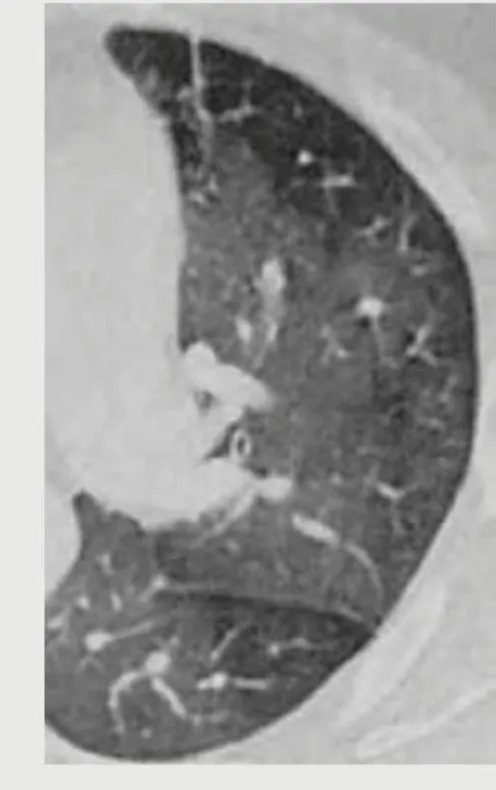

- HP pattern: centrilobular nodules + ground-glass + mosaic attenuation

| HP (chronic) | Centrilobular nodules + ground-glass + fibrosis | <50% in fibrotic | Lymphocytosis >30%, CD4/CD8 <1 | Poorly formed granulomas | Avoidance + steroids variable |